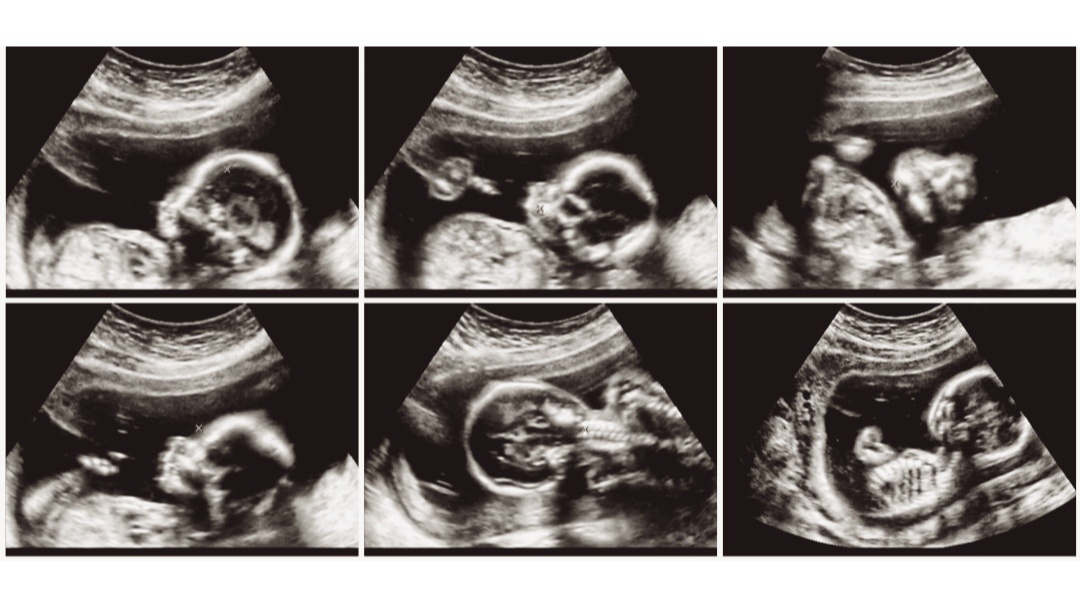

Каково же было моё удивление, когда после УЗИ врач с широко открытыми глазами сказала мне: «Лена, вы на 29-й неделе беременности». Я просто не могла поверить своим ушам. Почти семь месяцев! Я ничего не чувствовала, не замечала, списывала всё на лишний вес и усталость. Это был шок.